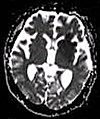

| Diffusion weighted (DWI) | Conventional | DWI | Measure of Brownian motion of water molecules.[66] | High signal within minutes of cerebral infarction (pictured).[67] |

|